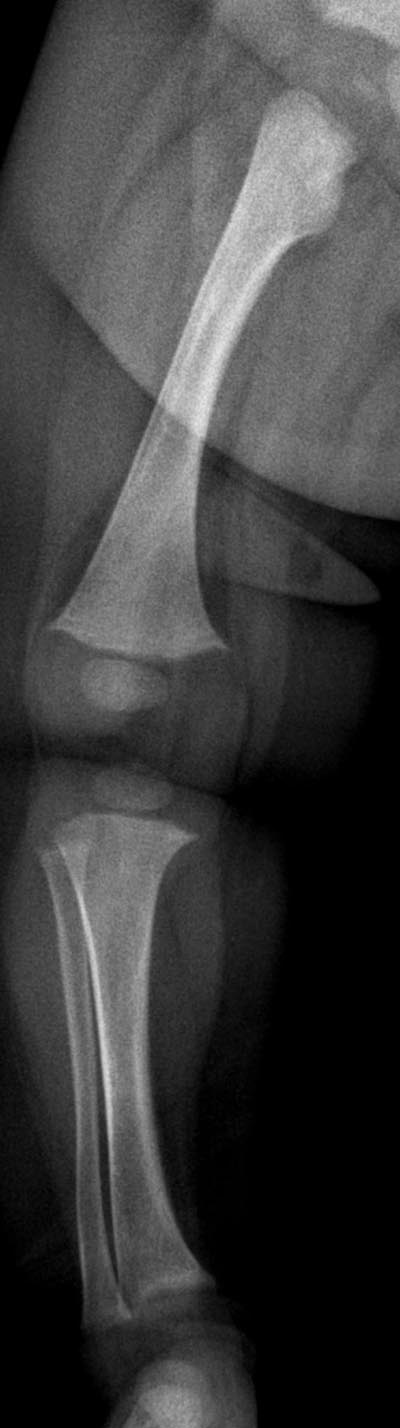

7 个月女孩,临床怀疑先天性髋脱位

干骺端宽大,杯口状变形,两侧出现骨刺,骨干增粗、骨膜增厚,考虑维生素d缺乏性佝偻病。

支持--干骺端宽大,杯口状变形,两侧出现骨刺,骨干增粗、骨膜增厚,考虑维生素d缺乏性佝偻病。建议拍肘关节正位片排除有无尺桡骨近端骨性连接。

干骺端宽大,杯口状变形,除此外还有股骨干的弯曲,另外干骺端骨质清楚,没有毛刷样表现。

请考虑一下有没有先天性疾病的可能?

请结合临床一定要除外厚皮性骨膜病,后者多发于1y以内,男性多见,以管状骨的骨膜增生和骨膜新骨形成为特征,为一致性连续性骨膜增厚,主要在尺、桡骨及胫、腓骨中下段,随病程进展可使骨膜变成成熟骨组织致骨干增粗,皮质增厚,关节囊等周围组织增生致关节肥大,但临床上有多汗、多脂以及皮下纤维组织增生的特点。

本例主要表现还应是一致性连续性骨膜增厚,虽表现为干骺端宽大,杯口状变形,但无毛刷状改变,骨减少亦不明确,故个人不支持佝偻病表现,股骨弯曲我认为是正常表现,虽然后者亦可出现骨膜反应,但为次要表现且如此连续的骨膜反应还是没见过;

另外,1 正常生理性骨膜炎:部分早产儿和婴儿可在桡骨干和股骨干见单层平行的骨膜反应,对称发生,随年龄增长而自然消失;但本例为双层,且无双侧对比,请酌。2 亦需从临床上排除婴儿骨皮质增生症,较易。3 gaucher病:一致性骨膜增厚,伴股骨下段烧瓶状膨胀,且髋部表特殊表现--股骨颈低头俯视,但本例多有骨质破坏和肝脾肿大等,不太支持。